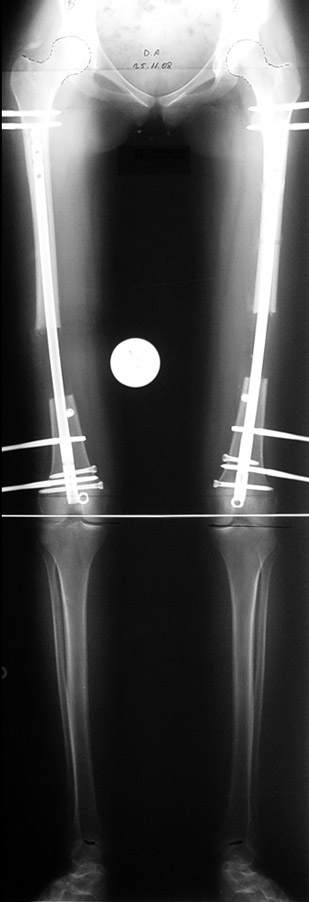

The patient lies is supine position at a traction table and legs are crossed with the uninvolved leg at the bottom. The medullary cavity is penetrated through piriform fossa using the standard method, and medulla is reamed 1.5 mm thicker than the nail to be used, over a guidewire. Proximal femur is reamed more, because the intramedullary nail is thicker proximally. The osteotomy site is planned at the X-Rays. It is important that at least 8 cm. of nail remains distal to the osteotomy site after the completion of the lengthening procedure. Percutaneous corticotomy is performed. The guide wire is advanced distally in order to measure the length of the nail. An intramedullary nail of apropriate length is placed. In the end, the nail is interlocked proximally, a suction drain is placed and the fist step of the operation is completed.

The application of the external fixator: Three Schanz screws are placed distally and three screws are placed proximally. At least 1 mm of distance shall remain between the screws and the nail.

In selected cases, we prefer to use a combination of a unilateral dynamic axial fixator and an interlocked intramedullary nail, in order to protect the length and alignment after the completion of the lengthening procedure. As a prerequisite for this technique, the narowest diameter of the medullary cavity shall be wider than 7 mm and the length of the nail segment distal to the osteotomy site shall be at least 8 cm. after the completion of the lengthening procedure.The intramedullary nail neutralizes shear and bending forces on femur during lengthening, shortens external fixation time, and protects newly formed bone against fractures. In our series, subtrochanteric osteotomy was performed in one case. No varus angulation occured despite the intramedullary nail.

Ilizarov stressed the significance of endosteal blood circulation for distraction osteogenesis. Although we placed the intramedullary nail after reaming the femur in all cases, the time for callus formation was not longer than expected. Thus we found that there is no slowing in the rate of new bone formation due to disruption of medullary blood flow. The rationale of this finding is revascularization that occurs following reaming of the medullary cavity, the fixation stability with the intramedullary nail and early functional weight bearing. The potential disadvantages of a combined use of external and internal fixation metods are increased blood loss, intramedullary infection, risk of fat embolism and excessive metal load.The most fearsome complication is a deep intramedullary infection (panosteomyelitis) triggered by pin tract infection.No such complication was encountered in our series. In order to avoid this complication, after the completion of lengthening the nail shaill be interlocked from the medial side, and contact of internal and external fixator pins shall be avoided.